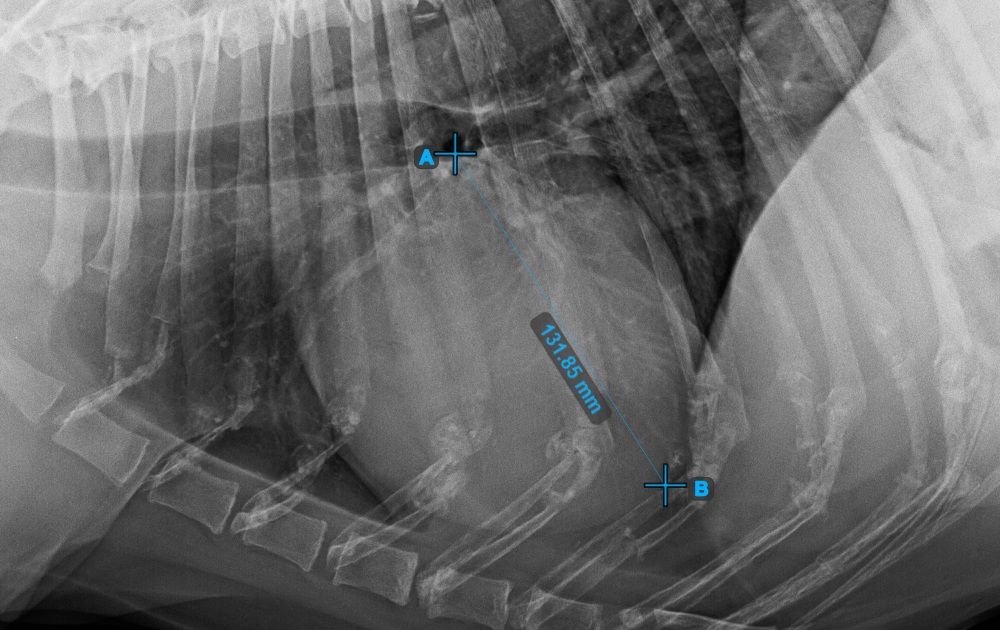

The image below represents a typical placement of the Apex point.

../../_images/image394.jpg